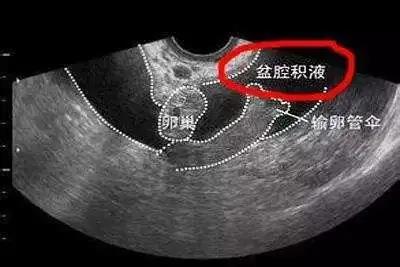

盆腔积液确切地说是影像学对盆腔内液体的一种描述,分为生理性盆腔积液和病理性盆腔积液两种。

生理性的盆腔积液多发生在排卵后或早孕期,正常值应<10MM左右,多可自然消失,不必进行治疗。

部分正常女性在月经期或排卵期会有少量的盆腔积液。如月经时,少量经血逆流至盆腔可造成盆腔积液;月经中期排卵时的卵泡液积在盆腔也可导致盆腔积液;便秘的患者,由于肠蠕动不正常,也可引起少量肠液渗出导致盆腔积液。

引起病理性盆腔积液的妇科疾病较多,如盆腔炎、异位妊娠、黄体破裂、盆腔结核、子宫内膜异位症等,这些疾病都可能会引起盆腔积液变多导致出现下腹部疼痛,坠胀,阴道分泌物增多的症状表现。